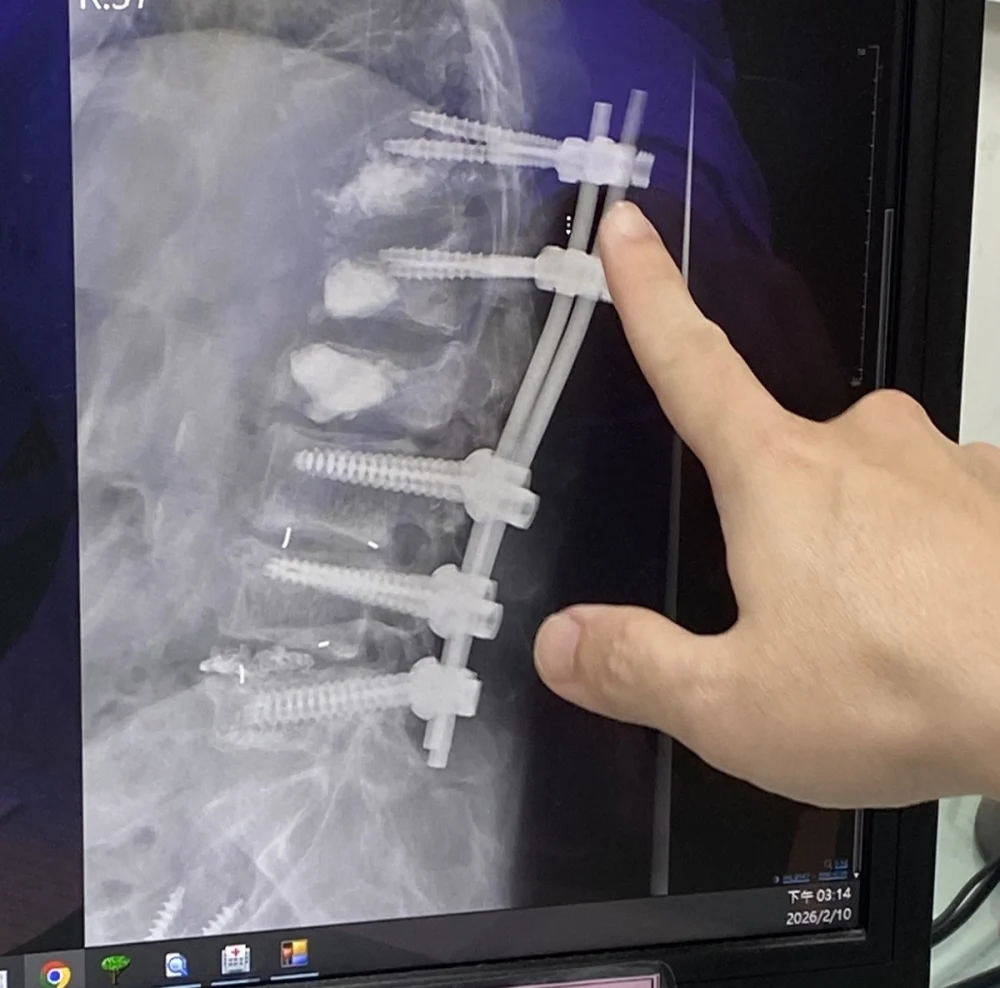

婦人表示,因腰痛、背痛,做了許多治療,也吃止痛藥、復健效果有限,仍背痛難耐在某醫院骨科醫師建議下,動了手術,然而手術後依舊疼痛,之後又連續動四次手術,也灌了骨水泥。手術後,背痛程度仍然劇烈,而且漸漸就越來越不能走。她躺著的時候輾轉反側,翻身也痛,正躺也痛;要走路、站也站不住,肩膀及右側髖關節也曾因跌倒骨折。

呂醫師說,患者剛來門診時,是由她先生推輪椅,把她推到床邊,她掙扎地爬到診療床上。呂醫師翻開患者背部看到五到八道疤痕,都是手術後留下的,疤痕硬的程度,用一般針灸幾乎刺不進去。像那種疤痕,僵硬也會造成疼痛,造成肌肉協調異常,這一部分是用針刀處理,因為一般的針已經刺不進去了。